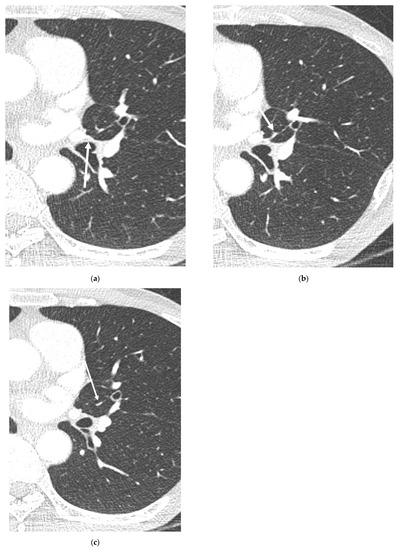

3. Results

3.2. Lobar and Segmental Supply Patternf of the AP

3.4. Presence of Other Accompanying Variations

4. Discussion